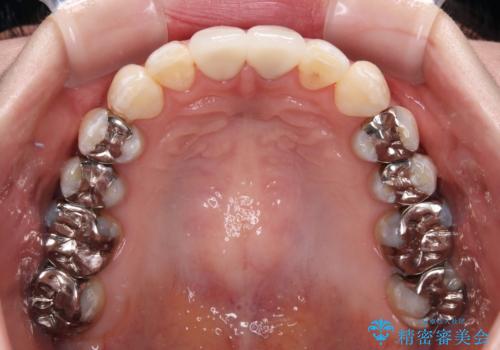

前歯を早々に仮歯に置き換えたことで、矯正治療に意欲的に臨んでくださいました。

口元が前方に突出することもなく、綺麗に仕上げることができました。